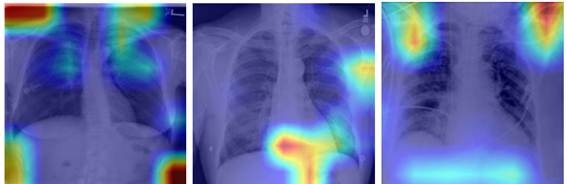

La figura 2 muestra el mapa de activación para una modificación de la CNN COVID-Net,33 obtenida a partir del método Grad-Cam, se usó toda la imagen para realizar la clasificación. Obsérvese que en todos los casos las regiones en las que se basa la red para realizar la clasificación están fuera de los pulmones. Esto significa que hay regiones que proporcionan suficiente información para separar adecuadamente las clases, pero las características utilizadas para la clasificación no están relacionadas con la enfermedad que se intenta clasificar. En otras palabras, el modelo sufre de aprendizaje por atajo. (Figura 2).

En el trabajo de Tsiknakis 35 se evaluó el resultado de los mapas de atención por dos radiólogos. Estos reportan que el modelo, la mitad de las veces, se centró en regiones fuera de los pulmones para realizar la clasificación. Por otro lado, en el estudio de De Grave y cols. 13 se aplicó la técnica CycleGAN, la cual generó imágenes sintéticas clasificadas correctamente por el clasificador. Estas imágenes generadas mostraron las marcas textuales como patrones importantes para determinar la clase. Asimismo, en otro trabajo se utilizaron mapas de saliencia, los cuales resaltaron con frecuencia los marcadores de lateralidad en las imágenes CXR, que difieren en estilo entre los conjuntos de datos COVID-19 negativo y COVID-19 positivo, y de forma similar resaltaron flechas y otras anotaciones que aparecen exclusivamente en el conjunto de datos.26